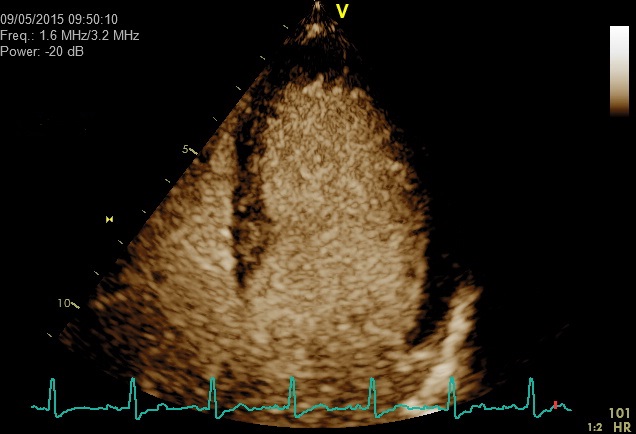

Linksherzkontrastmittel werden vor allem in der transthorakalen Echokardiographie eingesetzt, um bei eingeschränkt schallbaren Patienten eine verbesserte Darstellung insbesondere der linken Herzkammer zu erreichen (verbesserte Diagnostik von Störungen der Pumpfunktion). Es kann auch verwendet werden, um Strukturen wie z.B. ein Blutgerinnsel nach einem ausgedehnten Vorderwandinfarkt zu erkennen. Als Kontrastmittel wird SonoVue® eingesetzt.